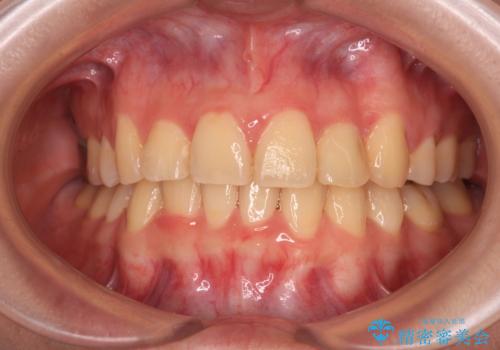

- 上下前歯のデコボコを気にして来院された患者様です。

歯列としては、ワイヤー装置でもインビザラインでも、どちらでも対応可能でしたが、処置されている歯が多く、ワイヤー装置を装着するためには処置歯のやり直しが必要な状態でした。

インビザラインでもアタッチメントを装着できないという同様のデメリットがありますが、比較的矯正治療を行いやすい歯列であったので、インビザラインによる矯正治療を行うこととしました。

術中や仕上がりに特に大きなトラブルはなく、スムーズに治療を終えることができました。